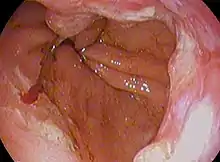

![]() | |

| Endoscopic image of Barrett's esophagus, which is the area of dark reddish-brown mucosa at the base of the esophagus. (Biopsies showed intestinal metaplasia.) | |

The main cause of Barrett's esophagus is thought to be an adaptation to chronic acid exposure from reflux esophagitis.[3] Barrett's esophagus is diagnosed by endoscopy: observing the characteristic appearance of this condition by direct inspection of the lower esophagus; followed by microscopic examination of tissue from the affected area obtained from biopsy. The cells of Barrett's esophagus are classified into four categories: nondysplastic, low-grade dysplasia, high-grade dysplasia, and frank carcinoma. High-grade dysplasia and early stages of adenocarcinoma may be treated by endoscopic resection or radiofrequency ablation.[4] Later stages of adenocarcinoma may be treated with surgical resection or palliation. Those with nondysplastic or low-grade dysplasia are managed by annual observation with endoscopy, or treatment with radiofrequency ablation. In high-grade dysplasia, the risk of developing cancer might be at 10% per patient-year or greater.[1]